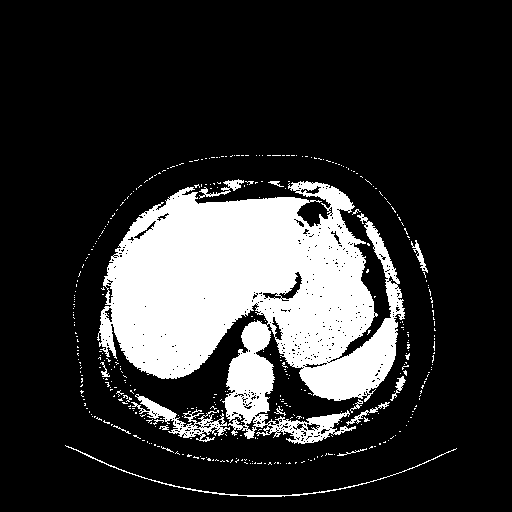

Generated VENOUS CT scan (A→B translation)

Full window (WL 1023.5, WW 4095 β†’ Low βˆ’1024, High +3071)

Actual HU range: [-1024.0, 3071.0]